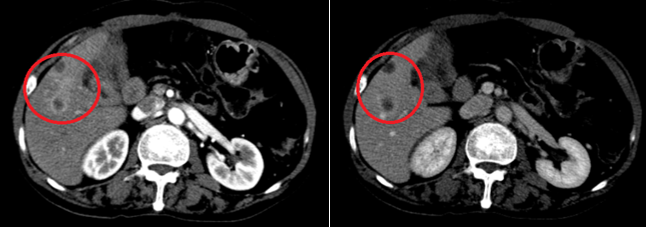

- Chụp cắt lớp vi tính ổ bụng: Hình ảnh hạ phân thùy V có 2 nốt ngấm thuốc kém, đường kính 14-15mm- theo dõi thứ phát. Thâm nhiễm dọc rễ mạc treo ruột non. Tĩnh mạch cửa không giãn, không có huyết khối.

Hình 1:  Hình ảnh chụp cắt lớp vi tính ổ bụng: Hạ phân thùy V có 2 nốt ngấm thuốc viền thì động mạch (vòng tròn màu đỏ)